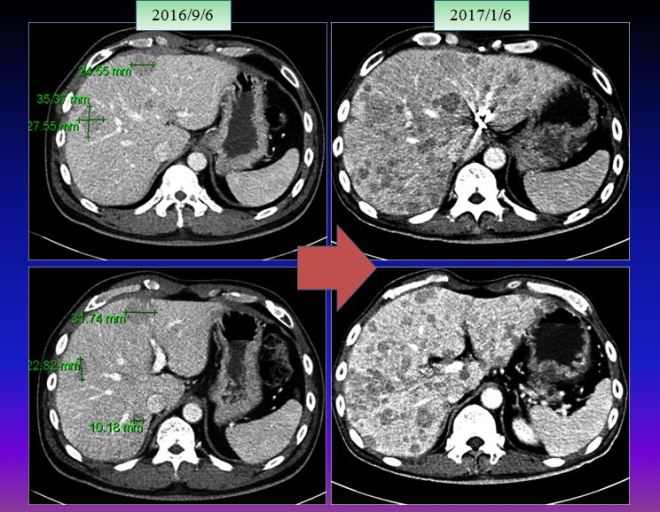

- 2012년 5월 간암발견 색전술을 1차 시행

- 2015년 -3년뒤- 다시 재발 고주파 치료 시행

- 2016년 11월 – 고주파 시술 후 22개월 뒤 간에 4개 종양재발

- 2016년 11월 28일 – 새로이 1.7cm 종양 보임 – 모두 5개 종양 발견

- 2017년 1월 5일 – 최초 진단 5년 만에 2차 색전술 시행

- 2017년 1월 20일 – 종격동(기관지 앞쪽)에 림프절 2개 발견 – 방사선치료

- 2017년 3월 9일 반룡인수한의원 내원 약 3cm의 종양 두개 보임. 한방치료 시작

- 2017년 5월 18일 두개의 종양 중에 하나는 소실됨. 또 하나는 면적대비 58 %로 감소됨

- 현재 한방 단독요법으로 치료 지속 중인 환자임

| 2017/3/9 | 강남 영상의학과 초음파 검사. S8. 2.1x 3.0cm S5 2.7x 3.0cm(WXD) | 초음파 검사 |

| 2017/3/31 | 강남 영상의학과 초음파 검사 com with 2017/3/9

2.1×3.0cm(WxD, S8) and 2.7×3.0cm(WxD,S5) -> 1.8 x 2.6cm(more regressed) and 2.7 x 3.2cm(no interval change) |

초음파 검사 |

| 2017/5/18 | ABDOMINAL SONOGRAM : Comparison with2017-03-30

1. Known HCC, post-TACE state 2. Previously noted an irregular hyperechoic lesion in the right hepatic lobe is seen again with more regression; (2.7 x 3.2cm ->1.8 x 2.8cm). Previously noted another hypoechoic lesion is not identified in this study. |

초음파 검사

두개 중에 하나는 없어지고 작은 것은 줄어들음 |

- 치료 시작 전 (2017/3/9) ABDOMINAL SONOGRAM :

- Known HCC, post-TACE state

- 2.1×3.0cm(WxD, S8) and 2.7×3.0cm(WxD,S5) sized irregular hyperechoic lesions in the right hepatic lobe, compatible with HCC

2. 치료 20일 뒤 (2017/3/31)

한방약물 단독 치료 20일 후 – 식이요법 소음인 식이요법으로 – 짜고 맵게 식사지도

강남 영상의학과 초음파 검사 com with 2017/3/9

2.1×3.0cm(WxD, S8) and 2.7×3.0cm(WxD,S5) -> 1.8 x 2.6cm(more regressed) and 2.7 x 3.2cm(no interval change)

3. 치료 두달 뒤 (2017/5/18) ABDOMINAL SONOGRAM : Comparison with2017-03-30

- previously noted an irregular hyperechoic lesion in the right hepatic lobe is seen again with more regression; (2.7 x 3.2cm ->1.8 x 2.8cm).

- Previously noted another hypoechoic lesion is not identified in this study.